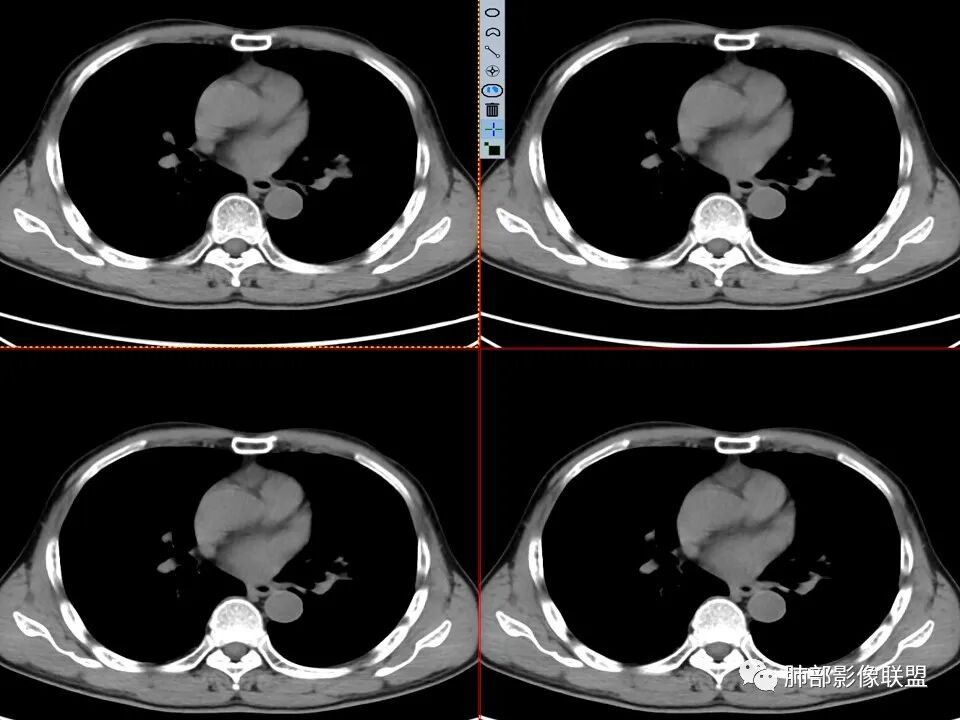

年龄不详,推测中老年人,因全身乏力就诊,CT发现左肺上叶结节灶,无明显咳嗽、发热等症状,无吸烟病史,配偶曾患“肺结核”,化验检查痰结核菌涂片阴性,CYFR轻度升高,PET-CT局部高摄取。

左肺上叶舌段近肺门区不规则结节,密度较均匀,结节边缘平直为主,可见粗短毛刺、毛刺偏软,浅分叶,收缩力不强,膨隆也不明显,周围可见模糊GGO,病灶内部支气管显示不清,病变远端支气管明显扩张,病灶与叶间裂呈宽基底相连,见刀切征,并见叶间裂多发结节影,叶间裂未见明显移位。

患者推测中老年人,无明显临床症状,肺气肿背景不明显,虽然病灶整体炎性征象较多,叶间胸膜多发结节,常规要考虑结核和腺癌,PET-CT肿瘤和炎性病变都可以高摄取,敏感性高,但特异性不高,而且腺癌周围缺乏清晰的磨玻璃及收缩力不强,故暂不考虑;虽然左肺上叶舌段病灶与支气管关系密切,如果周围磨玻璃推测为早期的阻塞性炎症,还有CYFR轻度升高,鳞癌不能除外,但是病灶的整体形态比较符合炎性改变。本病例可惜未行CT增强扫描,无法观察结节的强化特点及病灶内血管走行情况。